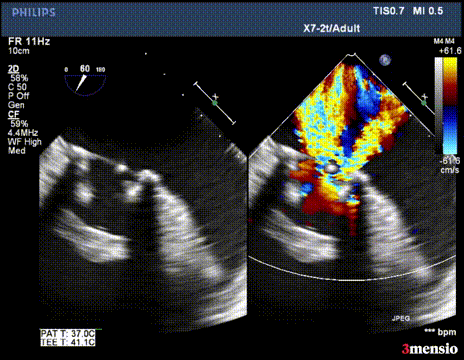

第二次切割后,导丝紧,血流分为两束

第二次切割后,导丝松,血流已打散

切割时拉紧导丝两端,不切割时,放松导丝,解除对瓣叶的压力后,用彩超观察血流方向,切割成功后,可以观察到彩超血流的改变。